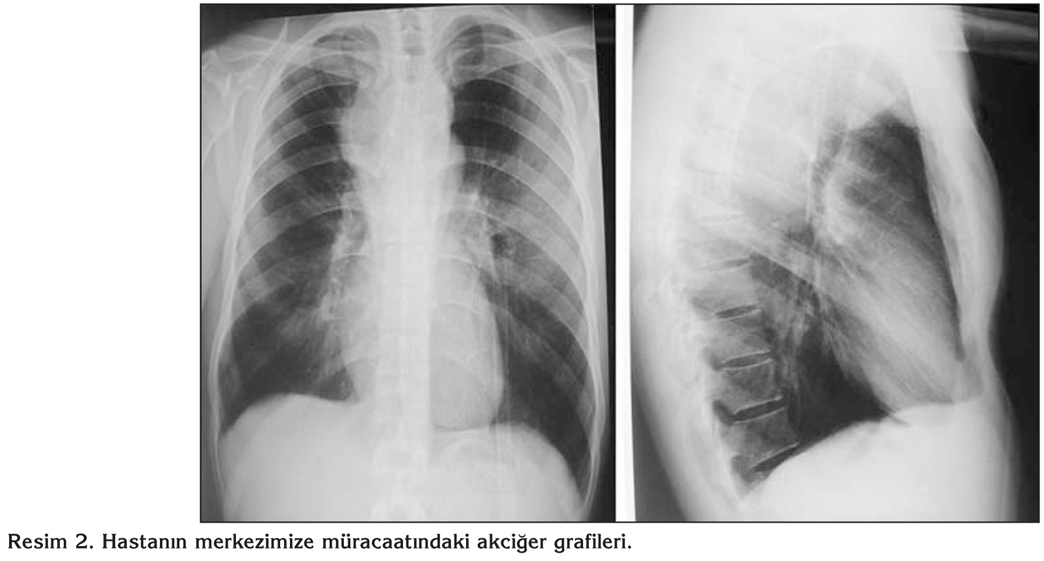

Yirmi bir ya??ndaki erkek hastaya, 2011 y?l? ?ubat ay?nda sol testiste a?r? ve ciltte ak?nt? ?ikayetiyle ba?vurdu?u merkezde, testiste kitle saptanarak, malignite ??phesiyle or?iektomi yap?lm??t?r. Hastan?n or?iektomi patolojisi kazeifiye gran?lomat?z iltihap olarak raporlanm?? olup, adli olgu/h?k?ml? olan hastan?n, kendisinden ve sevk i?lemlerinden kaynaklanan nedenlerle tedavisi ba?lanamam??. 2011 y?l? Eyl?l ay?nda g???s ve s?rt a?r?s? ve bu s?re zarf?nda yakla??k 10 kg kilo kayb?yla merkezimize ba?vuran olgunun g???s ?n y?z?nde fluktuasyon veren apse formasyonu d???nda fizik muayene bulgular?nda patoloji saptanmam??t?r (Resim 1). Laboratuvar incelemede; tam kan say?m? ve biyokimyasal de?erleri normal s?n?rlarda idi. Posteroanterior akci?er grafisinde paratrakeal dansite art???, yan grafide sternum ?n?nde yumu?ak doku art??? ile bombele?me mevcuttu (Resim 2). Toraks ve bat?n bilgisayarl? tomografi (BT) incelemesinde; toraks ?n duvar? sternum anteriorunda ve sol lateralinde, cilt alt? dokularda hipodens yer kaplay?c? lezyon, posterior mediastende paravertebral alanda en geni? yerinde 42 mm kal?nl??a ula?an vertebra korpusunda ve sa? kotlarda destr?ksiyona yol a?an heterojen dansitede yer kaplay?c? lezyon, sa? hemitoraks posteriorunda D10 vertebra korpusu solunda ve kotlarda destr?ksiyona yol a?an 40 x 25 mm boyutunda yumu?ak doku lezyonu, sa? hemitoraksta pl?rezi izlendi (Resim 3). G???s ?n y?z?nde fluktuasyon veren apseye yap?lan i?ne aspirasyonuyla p? aspire edildi ve Erlich Ziehl Neelsen aside diren?li boyama y?ntemiyle incelemede aside diren?li basil (ARB) g?r?lmedi. Apse materyalinin aerop ve anaerop k?lt?rlerinde ?reme olmad?. Al?nan balgam ?rne?inde direkt muayenede ARB negatif kald?. Yap?lan tetkikler sonucunda testis t?berk?lozunun yan? s?ra pl?rezi, g???s ?n duvar?nda so?uk apse, vertebra ?n y?z?nde paravertebral apse (Psoas apsesi), vertebralarda destr?ksiyon saptand?. Olguya testis t?berk?lozunun yan? s?ra yayg?n tutulum nedeniyle rifampin, izoniazid, pirazinamid ve etambutol olmak ?zere antit?berk?loz tedavi ba?land?. Merkezimize m?racaat?nda pl?rezide d?zelme mevcuttu (Resim 3B). Tedavi alt?nda, vertebra destr?ksiyonu a??s?ndan n?ro?ir?rji kons?ltasyonlar? devam eden hastan?n, tedaviye ra?men g???s ?n y?z?ndeki apsede d?zelme olmamas? ve hastan?n a?r? ve gerginlik ?ikayetleri olmas? nedeniyle g???s t?p? tak?ld? ve apse bo?alt?larak hasta rahatlat?ld? (Resim 3B). Takiplerde hastadan al?nan balgam ?rne?inin spesifik k?lt?r? negatif kald?. G???s ?n duvar?ndan aspire edilen p?den yap?lan spesifik k?lt?rde Mycobacterium tuberculosis ?redi. ?la? duyarl?l?k testlerinde diren? paterni saptanmad?. Vertebralara y?nelik ?ekilen manyetik rezonans g?r?nt?leme (MRG)'de; C5-6 diskinde posterior sa? paramedian prot?zyon, T1-T8 vertebralarda korpuslarda destr?ksiyon ve intervertebral foramen yoluyla spinal kanal i?ine uzanan 18 x 6.5 x 8.5 cm boyutlar?nda ankaps?le y?ksek dansiteli koleksiyon mevcuttu. Beyin ve sinir cerrahisi ile kons?lte edilen hastaya 2011 y?l? Aral?k ay?nda T3-T4 torakotomi + apse drenaj operasyonu yap?ld?. Postoperatif d?nemde ?ekilen MRG ile apsenin bo?alt?ld??? verifiye edildi. Tedavi sonras? lezyonlar geriledi ve yeni lezyon olu?mad? (Resim 4). Hasta halen ?ikayetsiz olup, t?berk?loz tedavisi sonland?r?lm??t?r. Hastal?k seyrine bak?ld???nda; adli olgu/h?k?ml? hastada, hastan?n kendisinden (hasta gecikmesi), sevk i?lemlerinden (sevk zincirinde gecikme) ve doktor gecikmelerinden (doktor gecikmesi) kaynaklanan yedi ayl?k bir tedavi gecikmesi olmu? ve ba?lang??taki testis t?berk?lozu, yayg?n t?berk?loz ile sonlanm??t?r.

Resim 2